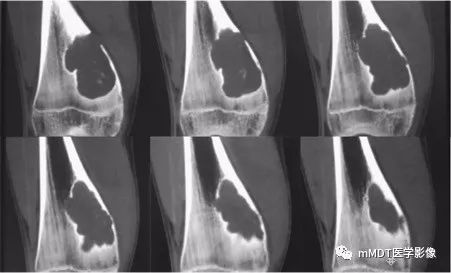

病史:15岁男性,右膝不适2年,行走及上楼时疼痛不明显。查体:右膝内侧膨隆,屈曲略受限,局部皮温正常,皮肤完整。影像资料如下:

CT冠状面骨窗

CT见病变位于股骨远端干骺端,呈分叶状、偏心膨胀性生长,密度欠均匀,整体低于肌肉密度,部分区域密度接近水,其内可见点状、线状、弧形、圆形的高密度影,大部分边缘硬化,局部深侵蚀骨内膜,局部骨壳不完整。MR上,T1WI信号略低于肌肉,T2压脂呈现不均匀高信号,未见明确软骨小叶结构及纤维分隔,周围可见水肿。